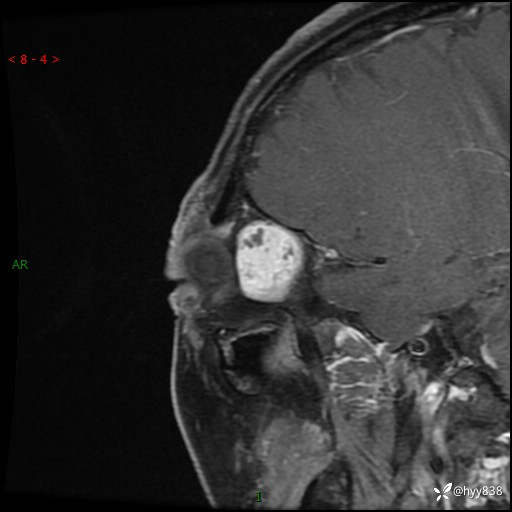

老年女性,右眼球突出1月。说说鉴别诊断,看谁第一个秒---(有结果)

主诉:发现右眼球突出1月余

简要病史:患者于1月前无明显诱因发现右眼球突出,偶感磨痛、眼胀,无视力下降,无头痛,恶心呕吐等不适。10天前就诊于当地县人民医院就诊,完善头颅ct检查,诊断为右侧眼眶肿物,建议患者上级医院进一步治疗,患者因个人原因拒绝。拟行手术,来我院就诊,门诊行相关检查后以“右眼眼眶肿物”收入院。 患病以来,患者精神饮食睡眠尚可,大小便如常、体重无明显改变。

辅助检查:MRI

临床诊断:眼眶肿物

眼眶MRI平扫+增强